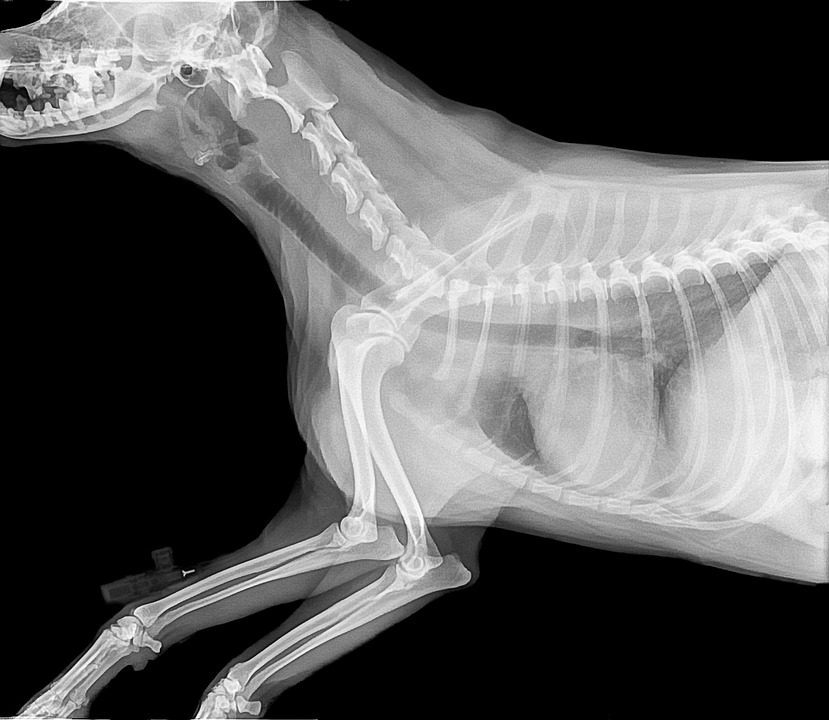

Nuestro servicio de radiología digital permite obtener imágenes de alta resolución de forma inmediata, facilitando el diagnóstico de fracturas, patologías torácicas, abdominales y articulares.

Radiología Digital

Imágenes instantáneas de alta resolución para diagnóstico óseo, torácico y abdominal